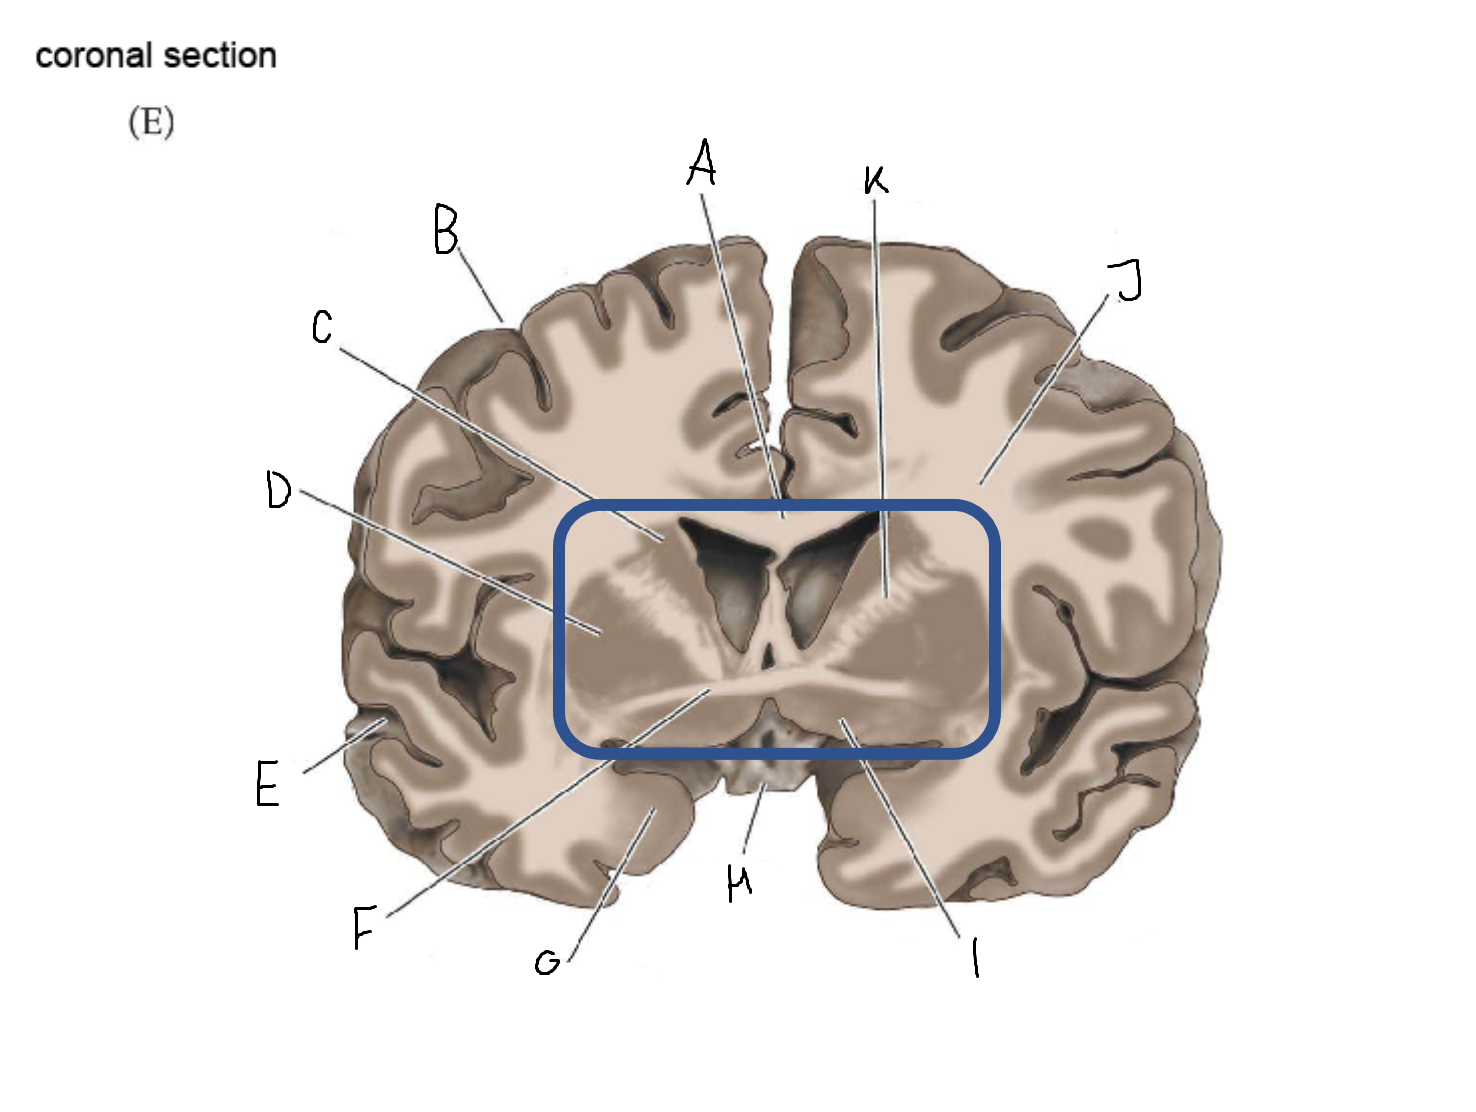

A

corpus callosum

B

cerebral cortex

C

caudate

D

putamen

F

anterior commissure

G

amygdala

H

optic chiasm

I

basal forebrain nuclei

K

internal capsule